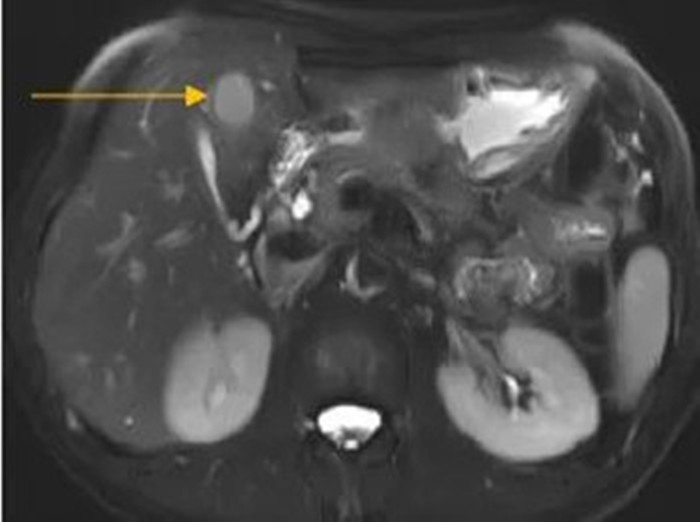

住院后經(jīng)胸腹部CT檢查,提示周先生胃部巨大腫塊穿破胃腔,可能累及到結(jié)腸,同時合并有胃旁淋巴結(jié)轉(zhuǎn)移、肝臟的轉(zhuǎn)移??吹竭@個檢查報告后,周先生和他的愛人一下子就泣不成聲了。

治療前肝臟的轉(zhuǎn)移灶